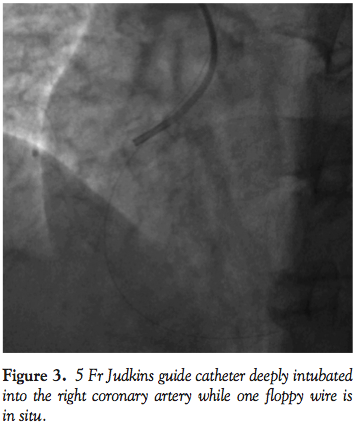

Another 0.014-inch choice floppy wire (Boston Scientific) was passed across the lesion. The 7 Fr guide catheter was withdrawn and a 5 Fr guide catheter was passed over the choice floppy wire (Figure 2), which was slowly intubated deep into the mid segment of the RCA (Figure 3). The choice floppy wire was then withdrawn while the stabilizer plus wire was kept in the artery. The hub of the guide catheter was disconnected from the Y-connector and a 20 mL Luer-Lok syringe (Becton-Dickinson) was attached. Maintaining a constant and moderate

these complications and achieve successful reperfusion. The lesion was crossed with 2 floppy wires. After initial angiogram with 7 Fr guide catheter and failure to achieve reperfusion with aspiration catheters, this guide catheter was exchanged over the 0.014-inch floppy wire with a 5 Fr guide catheter. This catheter was then deeply intubated up to mid RCA. One 0.014” wire was then withdrawn. Now the occluded RCA had an intubated 5 Fr guide catheter for thrombosuction and a 0.014-inch floppy wire going by the side of guide catheter up to distal RCA. The guide catheter was now withdrawn gradually into the aorta and then out of femoral sheath with continuous suction. While this was being done, one 0.014-inch wire was already in the RCA. This helped in 2 ways. First, even if artery was dissected due to guide, this wire ensured proper access to the distal RCA. Second, after withdrawing 5 Fr guide catheter, new 7 Fr guide was inserted over the existing wire. Hence, there was no need to recross the lesion. Post suction angiogram showed TIMI III flow in the RCA with no thrombus and residual stenosis in mid RCA. This residual stenosis was stented with a non-drug-eluting stent.